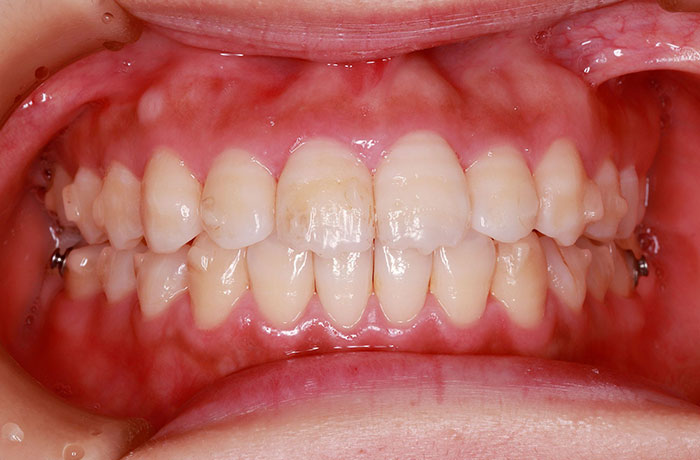

K様

治療後

年齢 27歳

性別 女性

治療名称 マウスピース型カスタムメイド矯正歯科装置(インビザライン)・コンプリヘンシブパッケージ(フルパッケージ)

総額治療費用 770,000円(税込10%) 金額備考 精密検査料・診断料 33,000円(税込10%)

治療期間 1年11か月 通院頻度など 40日ごと

1枚につき10日装着を指示しました。

治療内容

患者の症状 上顎前歯の前突、八重歯

治療方法 上下左右の第一小臼歯抜歯で、マウスピース型カスタムメイド矯正歯科装置による矯正

治療結果 上顎前歯の前突、八重歯が改善されました。

歯並びをより良くするために追加でアライナーを発注しました。

リスク/副作用 決められた時間装着する必要があります。